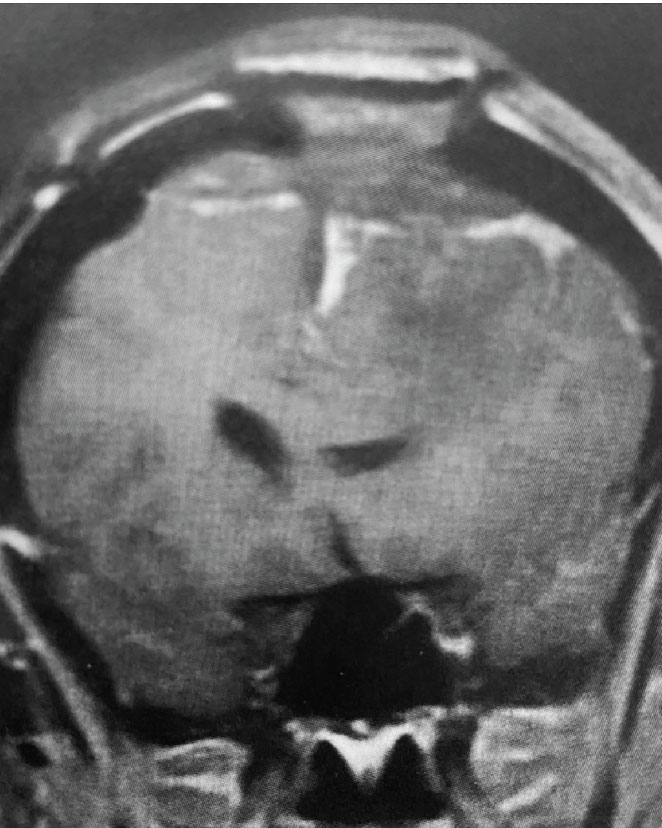

A) Pre-operative, post-contrast, coronal MRI. Arrow points to tumor involvement in the superior sagittal sinus

Fig 1. A) Pre-operative, post-contrast, coronal MRI. Arrow points to tumor involvement in the superior sagittal sinus.

This is a 55 year old right-handed woman who was having progressive balance problems. MRI with and without contrast demonstrated a 7 cm partly cystic meningioma involving the left frontal convexity and falx, and encasing the superior sagittal sinus. There was also tumor involvement of part of the convexity skull.